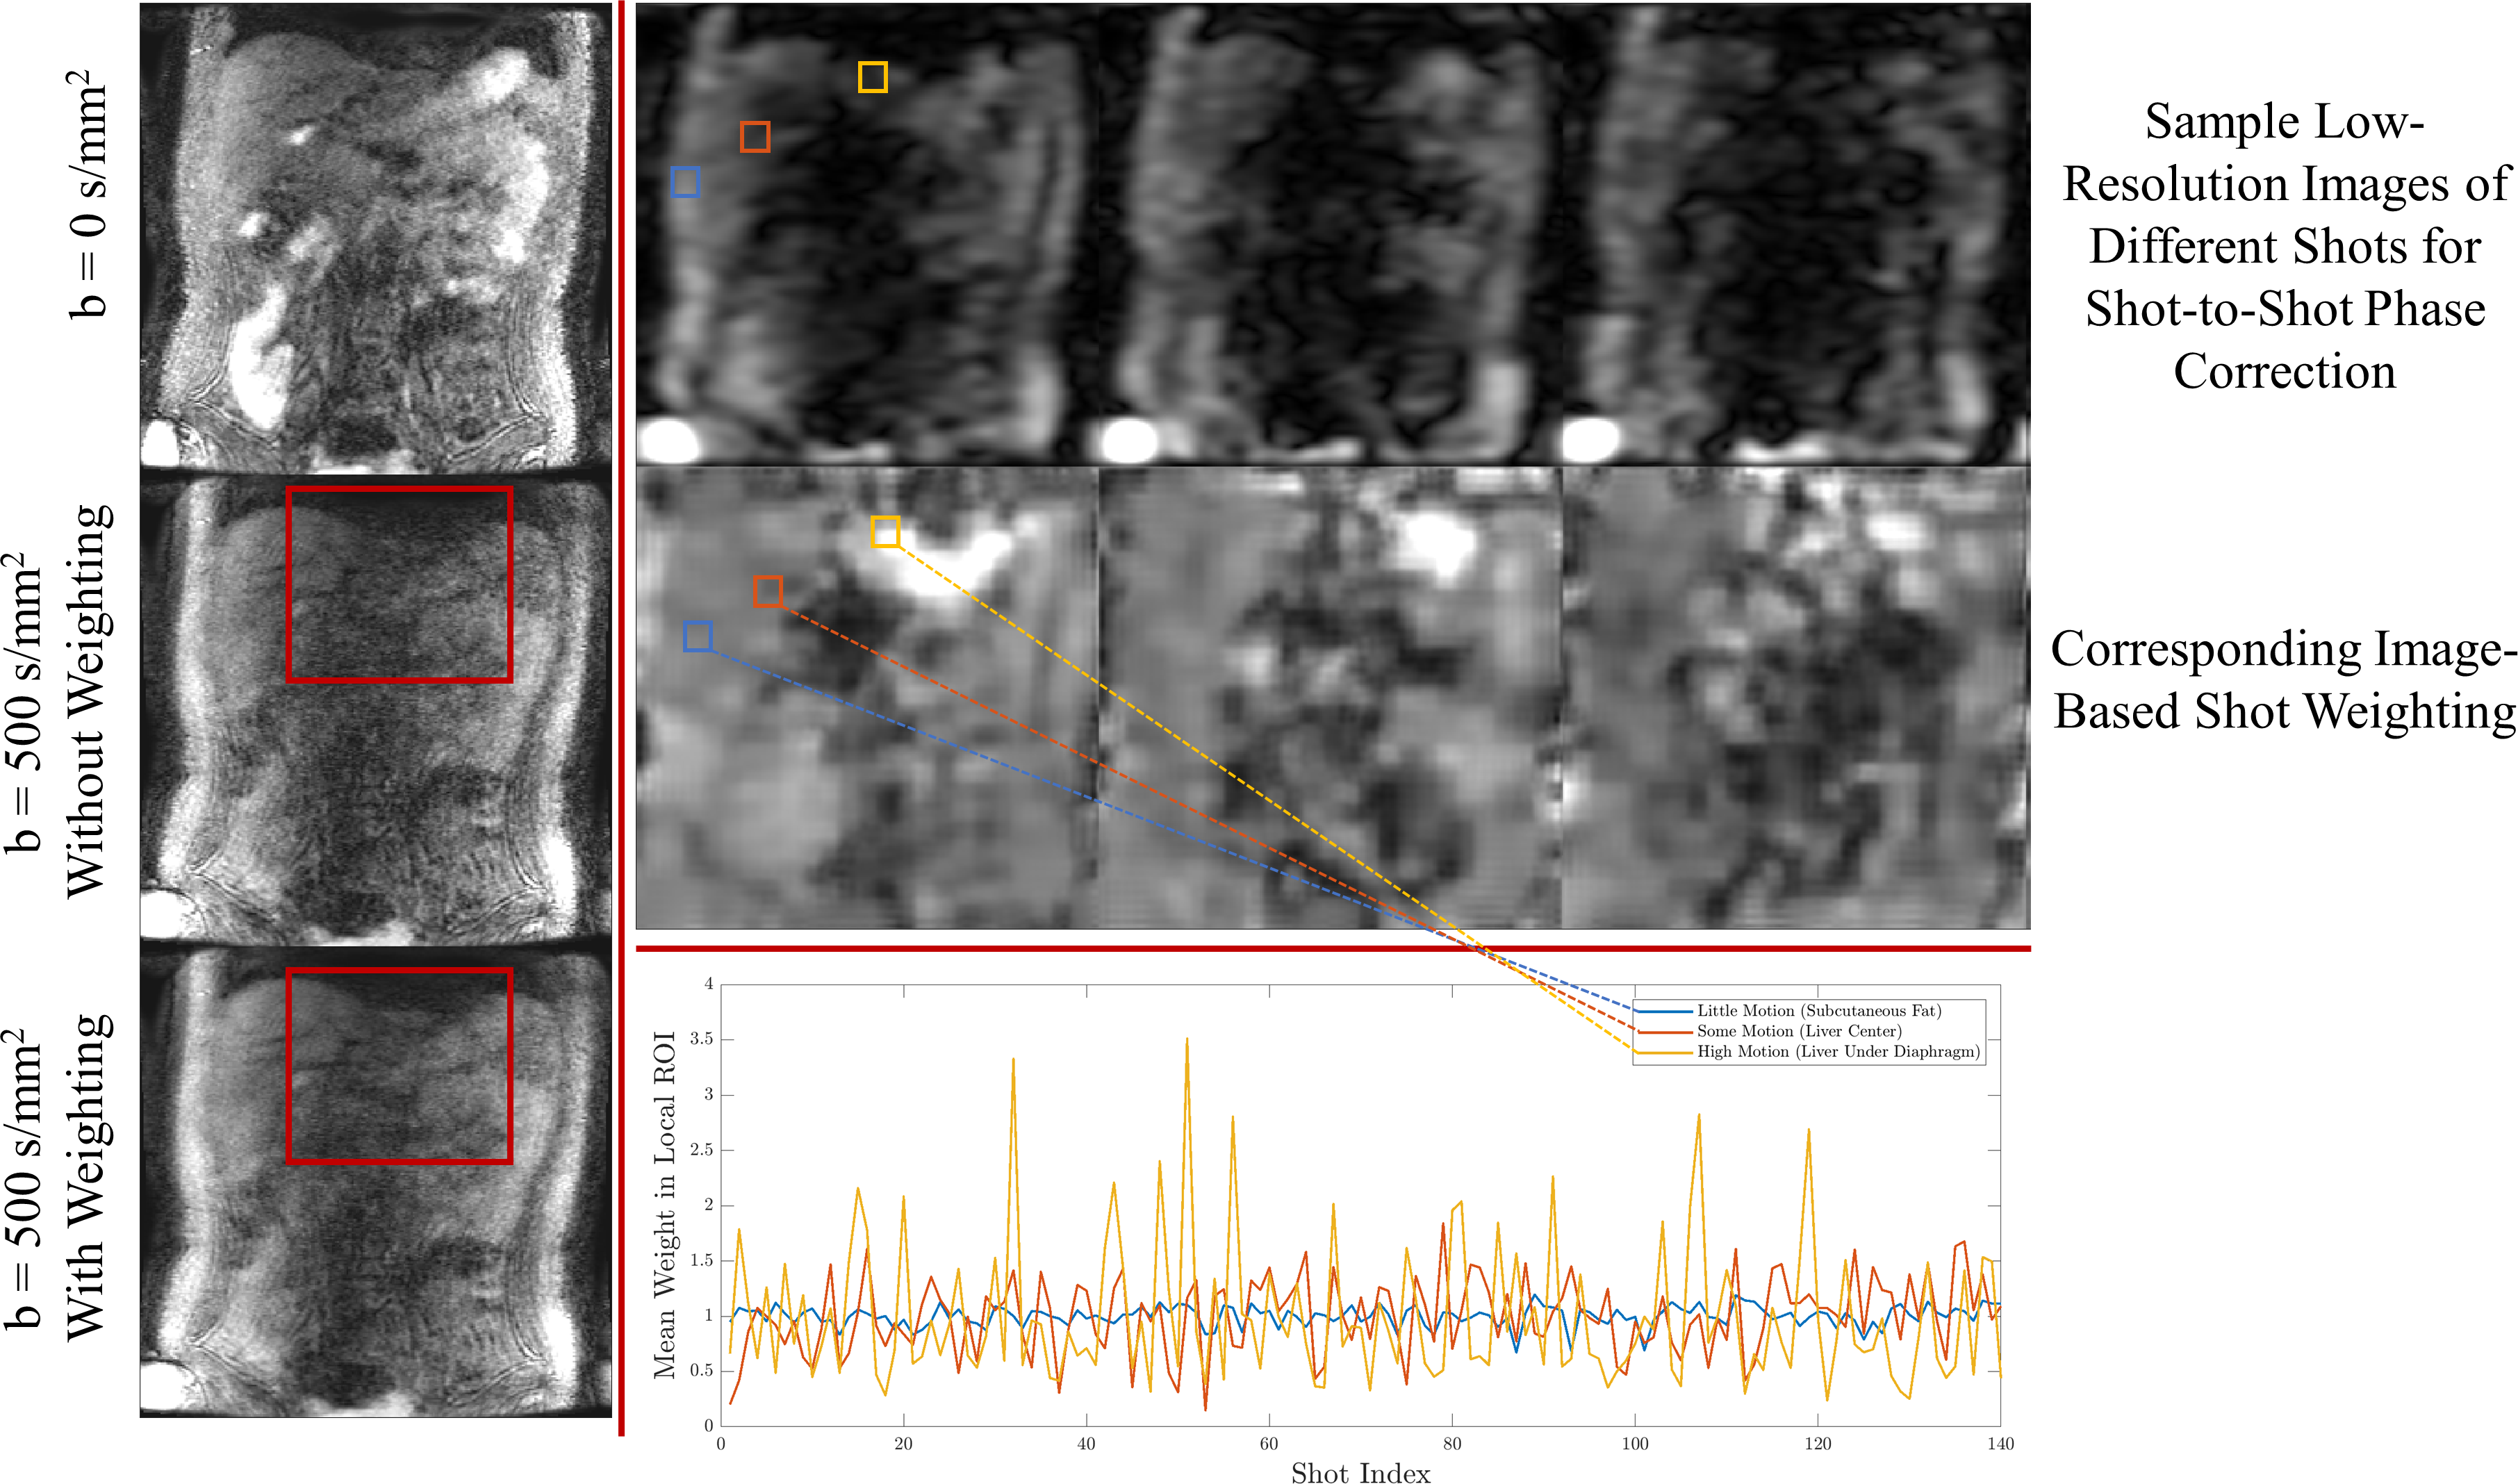

Image-based shot weighting: Because the degree of motion varies within the volume, diffusion gradients may annihilate signal in certain regions. Instead of discarding entire shots, we adopt an image-based per-shot weighting to deemphasize data overly corrupted by diffusion gradients4. The weighting is obtained from complex phase navigator images as the first right singular vector of local xyz-shots matrices, similar to Walsh coil estimation5. The weighting is a k-space convolution but is efficiently computed using zero-padded FFTs.

The effects of transient fat signal rephased during the readout is shown in the respiratory resolved images of Figure 2. Partial Fourier masking reduces these artifacts. Figure 3 shows the effect of high stabilizer area, which sensitizes the resolution to subvoxel motion. A smaller stabilizer area improves apparent resolution but introduces transient fat signal. Figure 4 shows a comparison with respiratory-triggered DW-EPI. Distortion in EPI is evident in the bowels and other organs. The proposed method is distortionless and has similar contrast. Figure 5 shows the benefit of shot weightings computed from phase navigators. Signal recovery is improved beneath the diaphragm, an area with high motion.

Figure 5: Image-based shot weighting improves signal recovery under the diaphragm (red box, left column), an area with high motion. Images used to compute weightings, as well as the generated weightings for three shots are shown (top right). The weightings for each shot in a small ROI are shown in the bottom right. Subcutaneous fat (blue square), which has little motion, has similar weighting between shots, whereas certain shots underneath the diaphragm (yellow square), are highly emphasized.